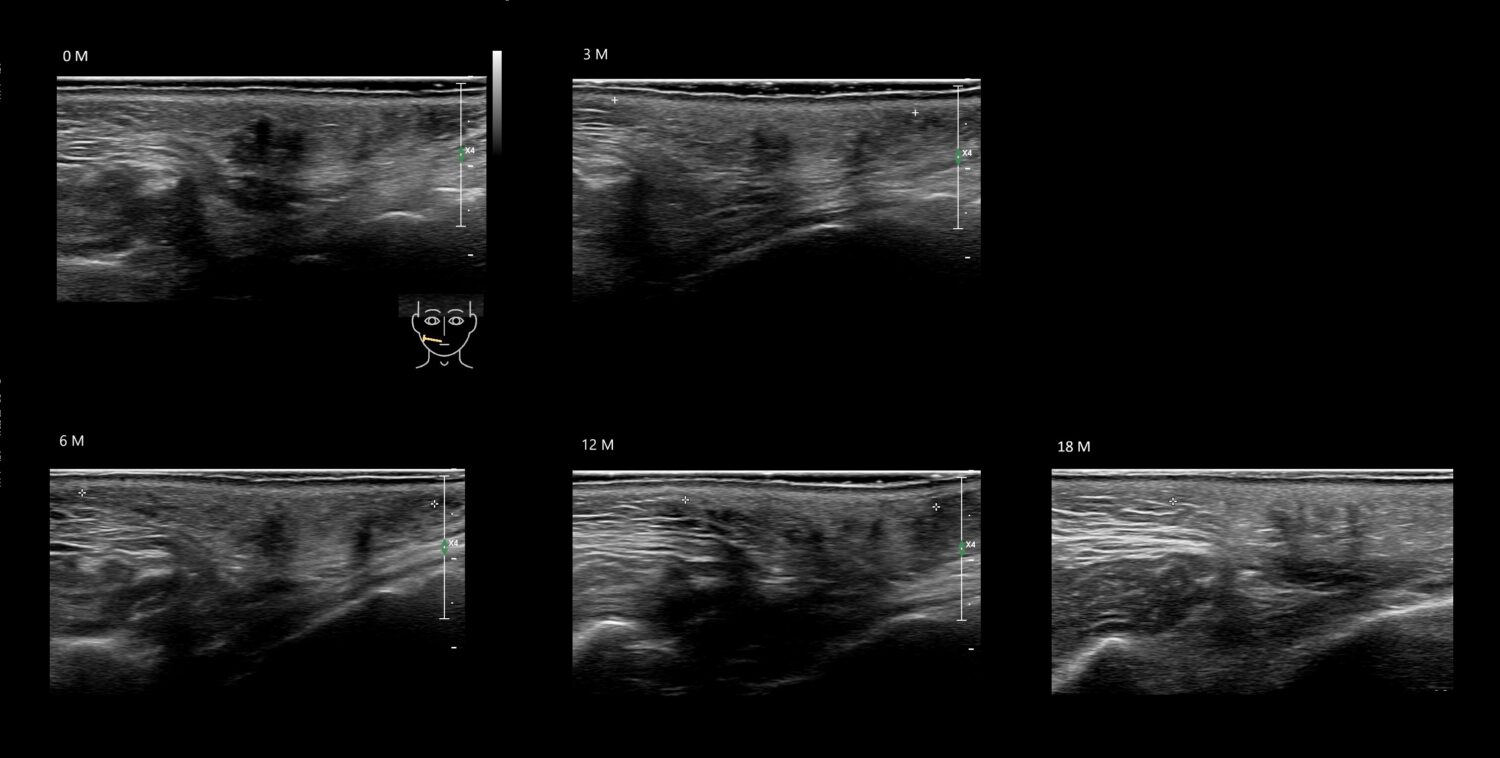

Filler library